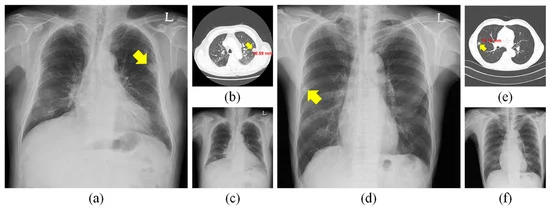

Automated Benign V/S Malignant Nodule in Chest X-ray

- Image Analysis: AI algorithms analyze chest X-ray images to identify and classify pulmonary nodules as benign or malignant based on their size, shape, density, margins, and other imaging features. These algorithms are trained on large datasets of annotated chest X-rays to learn patterns associated with different types of nodules.

- Feature Extraction: AI algorithms extract quantitative features from chest X-ray images, such as nodule size, shape irregularity, spiculation, calcification, and surrounding tissue characteristics. These features are used to develop predictive models that differentiate between benign and malignant nodules with high accuracy.

- Validation and Evaluation: Automated benign vs. malignant nodule detection systems undergo rigorous validation and evaluation to assess their performance and generalizability. This involves testing the algorithms on independent datasets, comparing their predictions with ground truth annotations provided by expert radiologists, and measuring metrics such as sensitivity, specificity, accuracy, and area under the receiver operating characteristic (ROC) curve.

- Risk Stratification and Patient Management: AI-powered nodule detection systems enable risk stratification and personalized patient management strategies based on the likelihood of malignancy. Patients with high-risk nodules may undergo additional imaging studies (e.g., CT scans), biopsy procedures, or referral to lung cancer specialists for further evaluation and treatment planning.